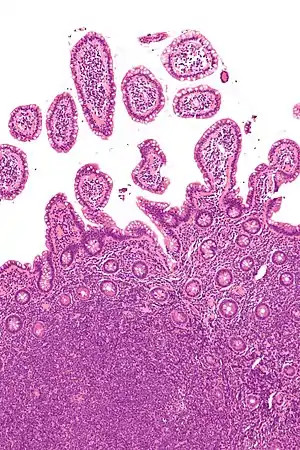

| Micrograph showing mantle cell lymphoma (bottom of image) in a biopsy of the terminal ileum. H&E stain. | |

MCL is a subtype of B-cell lymphoma, due to CD5 positive antigen-naive pregerminal center B-cell within the mantle zone that surrounds normal germinal center follicles. MCL cells generally over-express cyclin D1 due to the t(11:14) translocation,[6] a chromosomal translocation in the DNA.

A defining characteristic of MCL is mutation and overexpression of cyclin D1, a cell cycle gene, that contributes to the abnormal proliferation of the malignant cells. MCL cells may also be resistant to drug-induced apoptosis, making them harder to cure with chemotherapy or radiation. Cells affected by MCL proliferate in a nodular or diffuse pattern with two main cytologic variants, typical or blastic. Typical cases are small to intermediate-sized cells with irregular nuclei. Blastic (aka blastoid) variants have intermediate to large-sized cells with finely dispersed chromatin, and are more aggressive in nature.[16] The tumor cells accumulate in the lymphoid system, including lymph nodes and the spleen, with non-useful cells eventually rendering the system dysfunctional. MCL may also replace normal cells in the bone marrow, which impairs normal blood cell production.[17]

The history and physical examination may reveal some of the signs and symptoms consistent with Mantle Cell Lymphoma. Biopsy of the involved tissues (such as the lymph nodes, bone marrow, gastrointestinal tract, spleen or other areas) shows the characteristic histopathologic changes of MCL. There are distinct growth patterns of MCL seen on biopsy; these include the diffuse type, nodular type, mantle zone lymphoma and in situ mantle cell lymphoma.[7] In the diffuse growth pattern, there is a diffuse growth of lymphoma cells throughout the lymph node resulting in effacement of the architecture of the lymph node.[7] In the nodular type, there are large nodules of MCL cells in the lymph node with no germinal centers observed.[7] In MCL with expansion of the mantle zone, the lymphoma cells cause expansion of the mantle zone around normal germinal centers.[7] And in MCL in situ, the lymphoma cells are contained within the mantle zone without expansion.[7] Histologically, the lymphoma cells in classic MCL are characterized as small to medium lymphocytes with scant cytoplasm and clumped chromatin with prominent nuclear clefts and the nucleoli are not visible.[7] There are cytologic subtypes; the blastoid subtype, is characterized by round nuclei, fine chromatin with some distinct nucleoli.[7] The pleomorphic subtype is characterized by nuclei that vary in size and shape with some having a cleaved form.[7] The blastoid and pleomorphic subtypes of MCL are associated with a more aggressive course.[7]